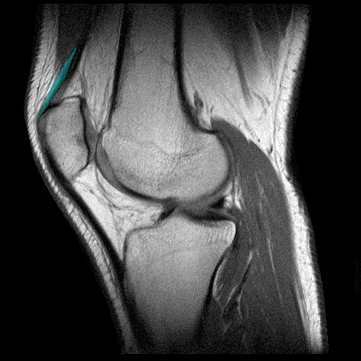

ANATOMIA DE LA RODILLA

TENDON DEL MUSCULO CUADRICEPS

Definici�n: El tend�n cuadriceps es la terminaci�n de cuatro m�sculos: recto anterior, vasto externo, crural, y vasto interno.

Origen:El recto anterior se origina en la espina il�aca. El vasto se origina en el femur superior lateral y posterolateral, debajo del troc�nter mayor. El crural se origina en la cara anterior del cuerpo del f�mur, debajo del tr�canter menor. El vasto interno se orgina en el labio interno de la l�nea �spera del f�mur. Los dos musculos vastos y el crural se unen distalmente al recto anterior para formar el tend�n cuadriceps. Esta configuraci�n es la que le otorga un aspecto trilaminar. Los �ngulos de inserci�n de los cuatro tendones en la r�dula contribuyen a estabilizarla ayudando a prevenir la subluxaci�n y dislocaci�n de la misma.

Inserci�n: El tend�n cuadriceps se inserta en la borde superior de la r�tula.

Funci�n: Los m�sculos del tend�n cuadriceps son los responsables de la extensi�n de la rodilla. El recto anterior tambi�n funiciona como flexor del muslo. El tend�n cuadriceps se rompe m�s frecuentemente a nivel de la junci�n tendino-�sea.